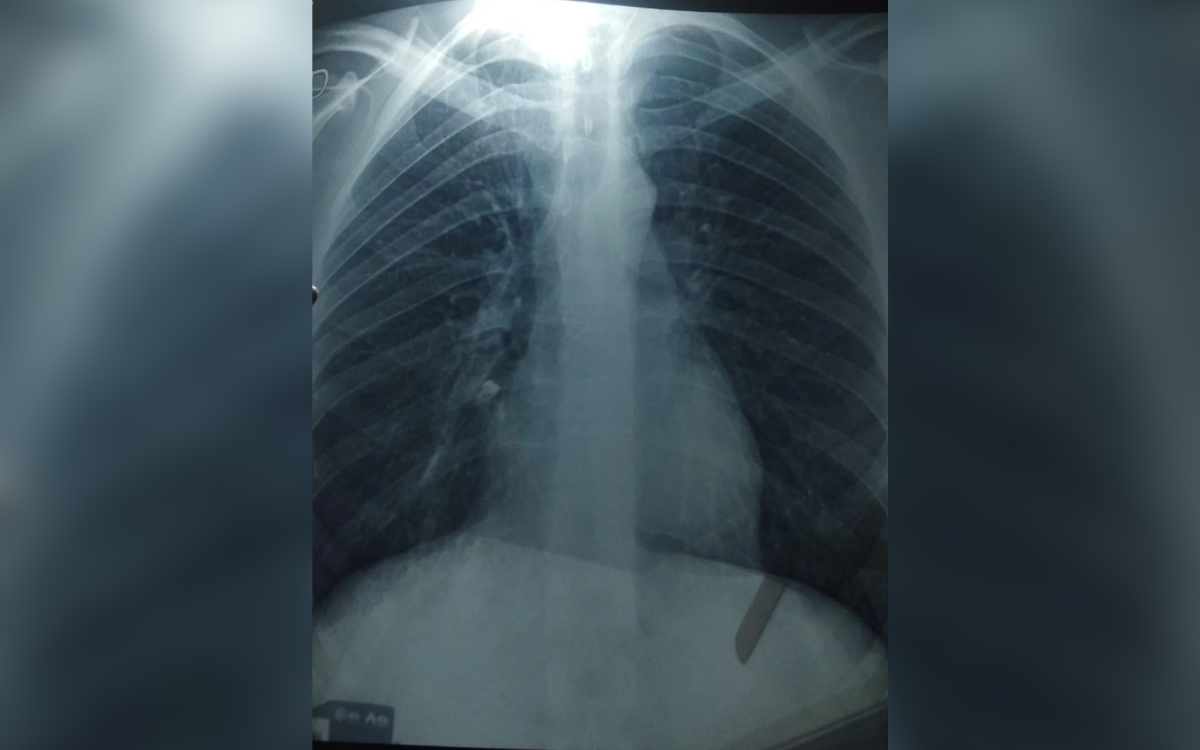

Artur said the hiccups were “very strong” and hurt his chest. When he then developed a fever, he decided to seek further help.